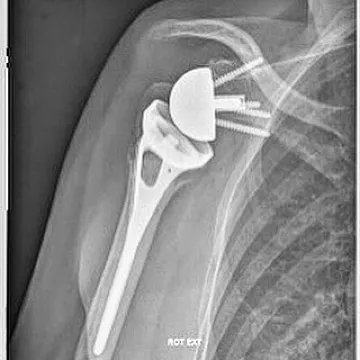

- la mise en place d'une prothèse de l'épaule si la fracture n'est pas synthésable, c'est à dire si les fragments osseux ne peuvent pas être remis en place. Cette prothèse d'épaule permet de reconstituer l'extremité supérieure de l'humerus mais aussi de redonner la fonction de l'epaule par l'intermédiaire des muscles intacts.

Le plus souvent une prothèse de type inversée est indiquée lorsqu'il existe des lésions associées des tendons de la coiffe des rotateurs ou lorsque la qualité osseuse des tubérosités est médiocre. C'est souvent le cas lors des fractures survenant chez des personnes âgées.

Une prothèse dite "anatomique" est indiquée dans certains cas lorsque les tendons de la coiffe de rotateurs sont fonctionnels et réparables (réparation des tubérosités) mais qu'il existe un risque de nécrose de la tête humérale important.

fracture luxation de l'épaule

prothèse inversée pour fracture de l'épaule